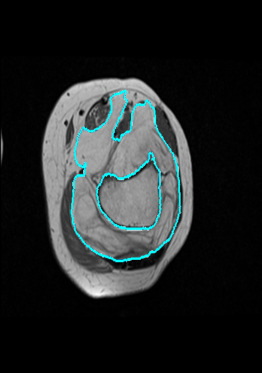

Radiomics uses quantitative medical imaging features to predict clinical outcomes. Currently, in a new clinical application, finding the optimal radiomics method out of the wide range of available options has to be done manually through a heuristic trial-and-error process. In this study we propose a framework for automatically optimizing the construction of radiomics workflows per application. To this end, we formulate radiomics as a modular workflow and include a large collection of common algorithms for each component. To optimize the workflow per application, we employ automated machine learning using a random search and ensembling. We evaluate our method in twelve different clinical applications, resulting in the following area under the curves: 1) liposarcoma (0.83); 2) desmoid-type fibromatosis (0.82); 3) primary liver tumors (0.80); 4) gastrointestinal stromal tumors (0.77); 5) colorectal liver metastases (0.61); 6) melanoma metastases (0.45); 7) hepatocellular carcinoma (0.75); 8) mesenteric fibrosis (0.80); 9) prostate cancer (0.72); 10) glioma (0.71); 11) Alzheimer's disease (0.87); and 12) head and neck cancer (0.84). We show that our framework has a competitive performance compared human experts, outperforms a radiomics baseline, and performs similar or superior to Bayesian optimization and more advanced ensemble approaches. Concluding, our method fully automatically optimizes the construction of radiomics workflows, thereby streamlining the search for radiomics biomarkers in new applications. To facilitate reproducibility and future research, we publicly release six datasets, the software implementation of our framework, and the code to reproduce this study.

翻译:放射科使用定量医学成像特征来预测临床结果。目前,在一个新的临床应用中,通过一个超常试验和高压过程,通过人工操作,从广泛的现有选项中找到最佳放射法。在本研究中,我们提议了一个框架,自动优化每个应用程序的放射工作流程的建设。为此,我们将放射作为模块工作流程,并包括每个部件的大量通用算法。为了优化每个应用程序的工作流程,我们使用随机搜索和聚合的自动机学习方法。我们用12种不同的临床应用来评估我们的方法,结果在曲线下应用的以下领域:1) 脂色瘤(0.83);2) 脱氧型纤维瘤(0.82);3 初级肝脏肿瘤(0.80);4 气肠肿瘤(0.77)、5 彩虹肝脏移植(0.61); 6 脑膜细胞变异常(0.45); 7) 肝细胞变异常(0.8) 脑纤维变异位(0.80); 9) 直径直线型癌症(0.74) 和头型癌症(0.77) 直径研究(10) 。